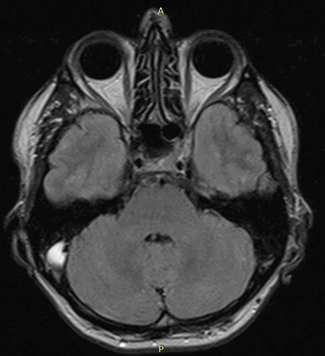

Рисунок 1. МРТ. Четырехкамерное сечение сердца. Стрелкой указан дефект межпредсердной перегородки (ДМПП).

Рисунок 2. МРТ. Аневризма нисходящего отдела аорты.

Рисунок 3. МРТ. Четырехкамерное сечение сердца. Апикальная гипертрофия миокарда левого желудочка.

Рисунок 4. МРТ. Четырехкамерное сечение сердца. Миокардит, субэпикардиальное и интрамиокардиальное накопление контрастного препарата.

Рисунок 5. МРТ. Двухкамерное сечение левого желудочка. Постинфарктный кардиосклероз.